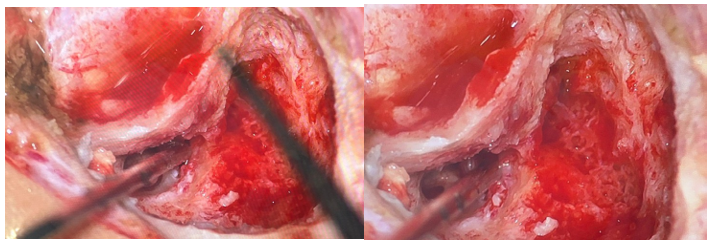

Based on the imaging findings and the severity of the electrophysiological lesion, surgical exploration was performed through a transmastoid approach one month after the trauma. A cortical mastoidectomy was first performed, followed by an antro-atticotomy to expose the short process of the incus, a key landmark for identifying the facial nerve. A wide posterior tympanotomy was then carried out, allowing decompression of the facial nerve at the level of its genu and mastoid segment. Intraoperative findings revealed a severely contused facial nerve at the second genu, consistent with axonotmesis, while neural continuity was preserved. Decompression of the tympanic and mastoid segments was achieved, and a temporalis fascia graft was interposed to protect and support the injured segment.

Figure 3: Per-operative image showing decompression of the facial canal at its second genu using a diamond burr

Figure 4: Per-operative image showing the appearance of the facial nerve after decompression

Figure 5: Per-operative image showing two aponeurotic grafts at the genu and the mastoid (third) segment of the facial nerve, through the posterior tympanotomy, the round window niche, the pyramidal eminence, and the stapes tendon were clearly visualized